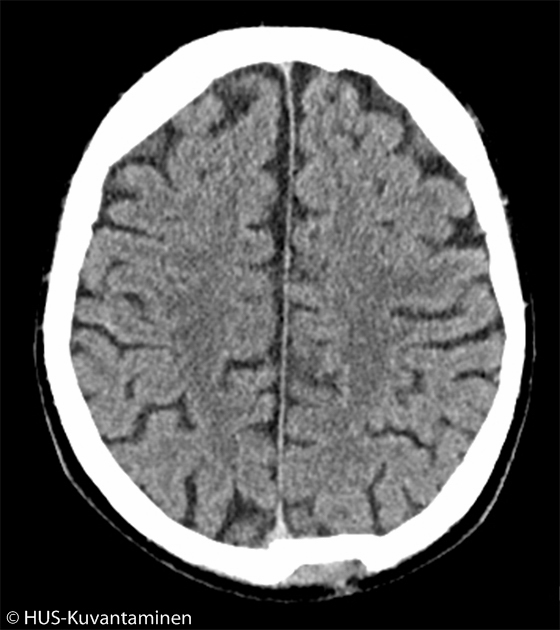

Kallonmurtuma pään TT-kuvassa (kuva 2 ilman löydösmerkintöjä),

Kuva: HUS-Kuvantaminen